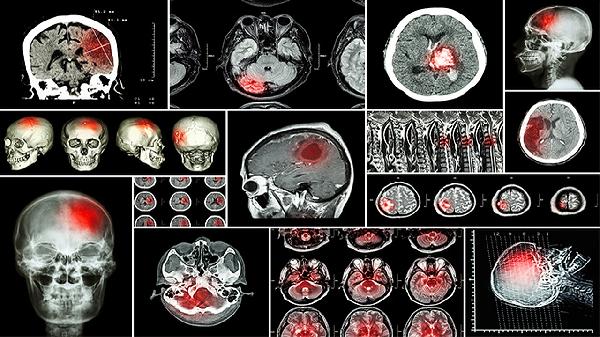

脑部磁共振主要用于检查脑部结构、功能和病变,包括肿瘤、脑血管疾病、炎症、先天畸形等。通过高分辨率成像,帮助医生精准诊断和制定治疗方案。

脑部磁共振可以检查多种疾病。脑肿瘤是常见检查对象,MRI能清晰显示肿瘤的位置、大小及与周围组织的关系。脑血管疾病如脑梗死、脑出血也能通过MRI明确诊断。MRI还能发现脑部炎症、感染、先天畸形等病变。对于癫痫、多发性硬化等神经系统疾病,MRI是重要的辅助诊断工具。